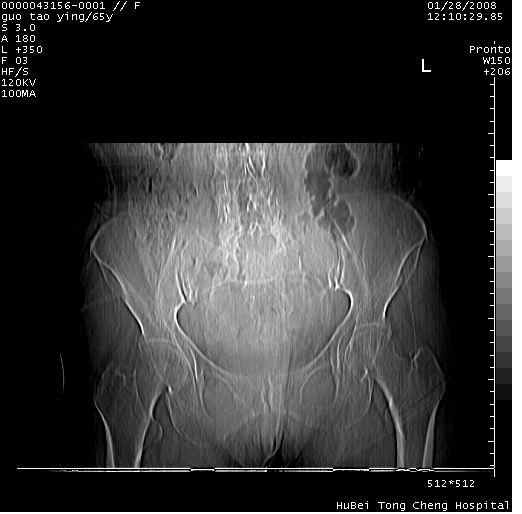

以下是引用黑白光影在2008-1-30 13:22:00的发言:[br]支持左耻骨骨折。[br]未见骶骨骨质明确破坏改变。[br]经楼主提示(勿局限于外伤)。考虑为右侧腹股沟直疝。[br][br][br][br]